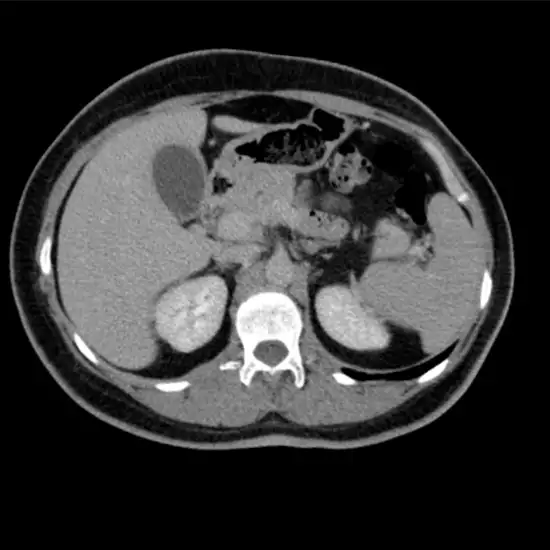

Dual Phase CT (Computed Tomography) Abdomen scan is an imaging scan that obtains cross-sectional images of the liver and pancreas at different optimal scanning times. This scan gives detailed information about the problems in the abdomen over the other imaging techniques such as X-ray. The doctor usually prescribes this scan to diagnose the problems in the abdominal structure. This test is used to diagnose the root cause of abdominal pain and tenderness. It helps diagnose the suspected perforation of the stomach, gallstones, and kidney stones. It is also helpful in detecting abnormal growth/cancer of the stomach, liver, pancreas, spleen, intestines, bladders, and surrounding soft tissues of the abdominal region.

DUAL Phase CT Abdomen (Computed Tomography) screening of the Abdomen is a non-invasive radiology test used to evaluate the abdomen and surrounding tissue. DUAL Phase CT Abdomen is done to look for the conditions of the abdomen and the surrounding area.